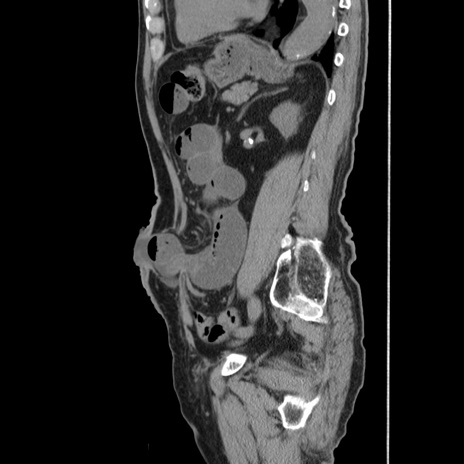

横断像

【症例】80歳代男性

【主訴】左側腹部痛、嘔吐

【現病歴】本日早朝より左腹部に痛みあり。昼頃嘔吐認めたため、救急要請。

【既往歴】直腸癌(Mile手術)、胆摘

【身体所見】意識清明、BT 35.9℃、BP 221/93mmHg、SpO2 97%(RA) 、腹部:左ストーマ周囲に限局性の腹部膨隆あり。 膨隆部自発痛・圧痛あり・軟。

【データ】WBC 7700、CRP 0.09